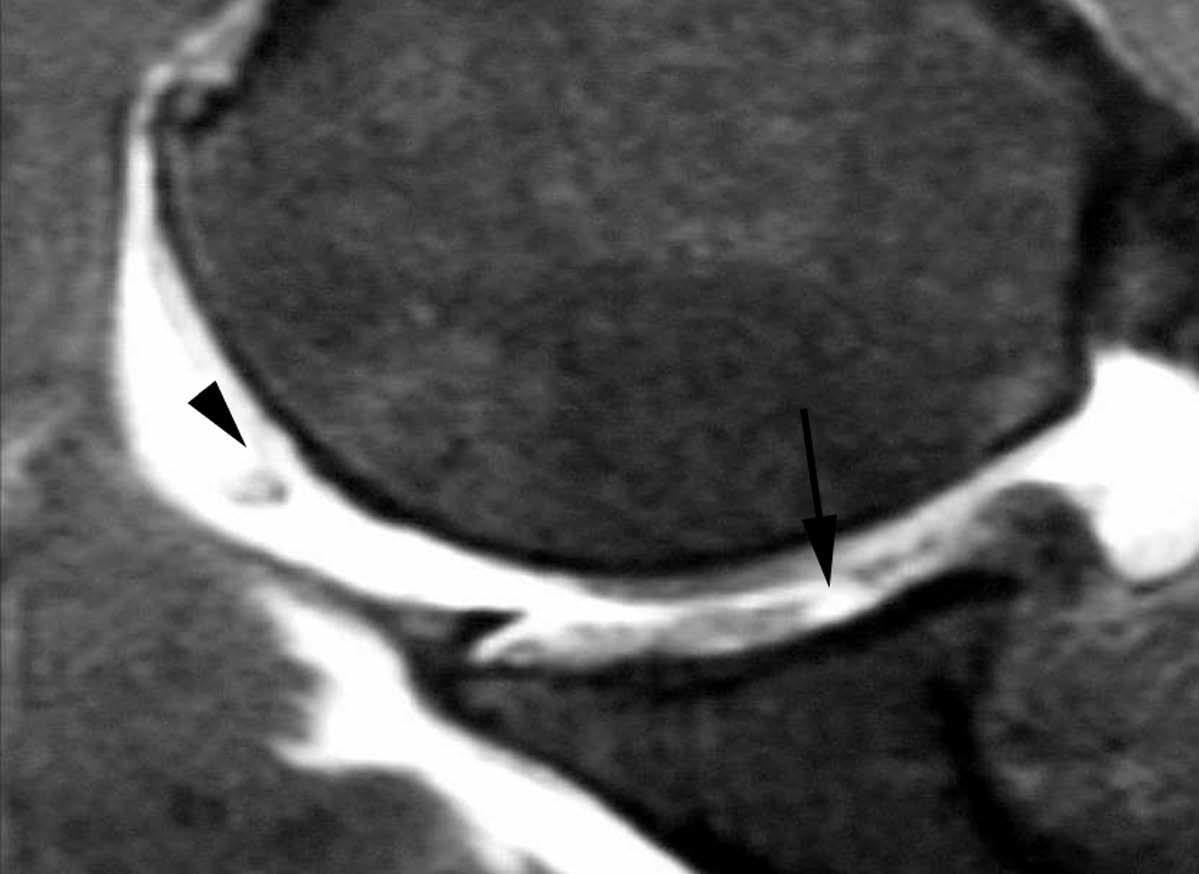

POLPSA (posterior labral periosteal sleeve avulsion)

Esta lesión se asemeja a la ALPSA, pero ocurre en el borde glenoideo posterior. El LG se halla desplazado hacia dentro y por detrás del borde glenoideo posterior. El mecanismo de producción del POLPSA es una dislocación posterior, y por tanto se puede encontrar también un Hill Sachs invertido19 (fig. 14).

. Artrorresonancia axial T1 con supresión grasa donde se observa una rotura del labio glenoideo posterior con desplazamiento posteromedial (flecha). Nótese la situación del labio glenoideo en comparación con una rotura sencilla, no desplazada, que se observa en la figura 13. Obsérvese la presencia de una lesión de Hill-Sachs invertida (cabezas de flecha), en relación con una dislocación posterior con reducción.Lesión de Bennett